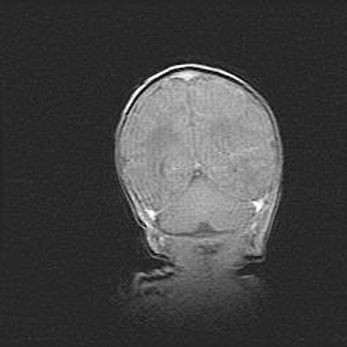

Сообщающаяся гидроцефалия. Кистозная энцефаломаляция головного мозга.

Возраст: 3 месяца 4 дня

Вес: 3100 г

Пол: женский

Окружность головы: 34 см

Срок гестации: 31 неделя

Кистозная энцефаломаляция головного мозга - одна из форм поражения головного мозга в детском возрасте. Характеризуется возникновением множественных и распространённых кист в коре, белом веществе и подкорковых образованиях головного мозга у плодов, новорождённых и детей раннего возраста. Развитие кистозной энцефаломаляции связано с внутриутробной асфиксией и гипотонией, родовой травмой, тромбозом синусов, пороками развития сосудов, инфекциями, сепсисом и другими причинами. Наиболее значимые инфекционные агенты: вирусы простого герпеса, цитомегалии, краснухи, токсоплазмы, энтеробактерии, золотистый стафилококк и другие.